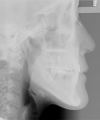

日本矯正歯科学会専門医課題症例(第7症例)

カテゴリー:開咬(overbiteがマイナスのもの)

| 治療後3年経過時